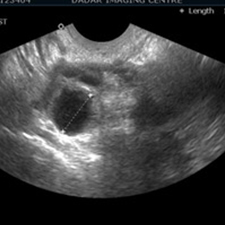

S.S.G(सोनोसालफिंगोग्राफी) गर्भाशयात विशिष्ट प्रकारचे औषध सोडून सोनोग्राफीच्या साहाय्याने गर्भाशय व नळयाची तपासणी